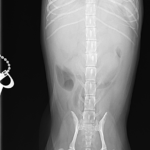

画像診断:特徴的な所見は述べらていませんが、CTで子宮の捻転基部が観察されました。